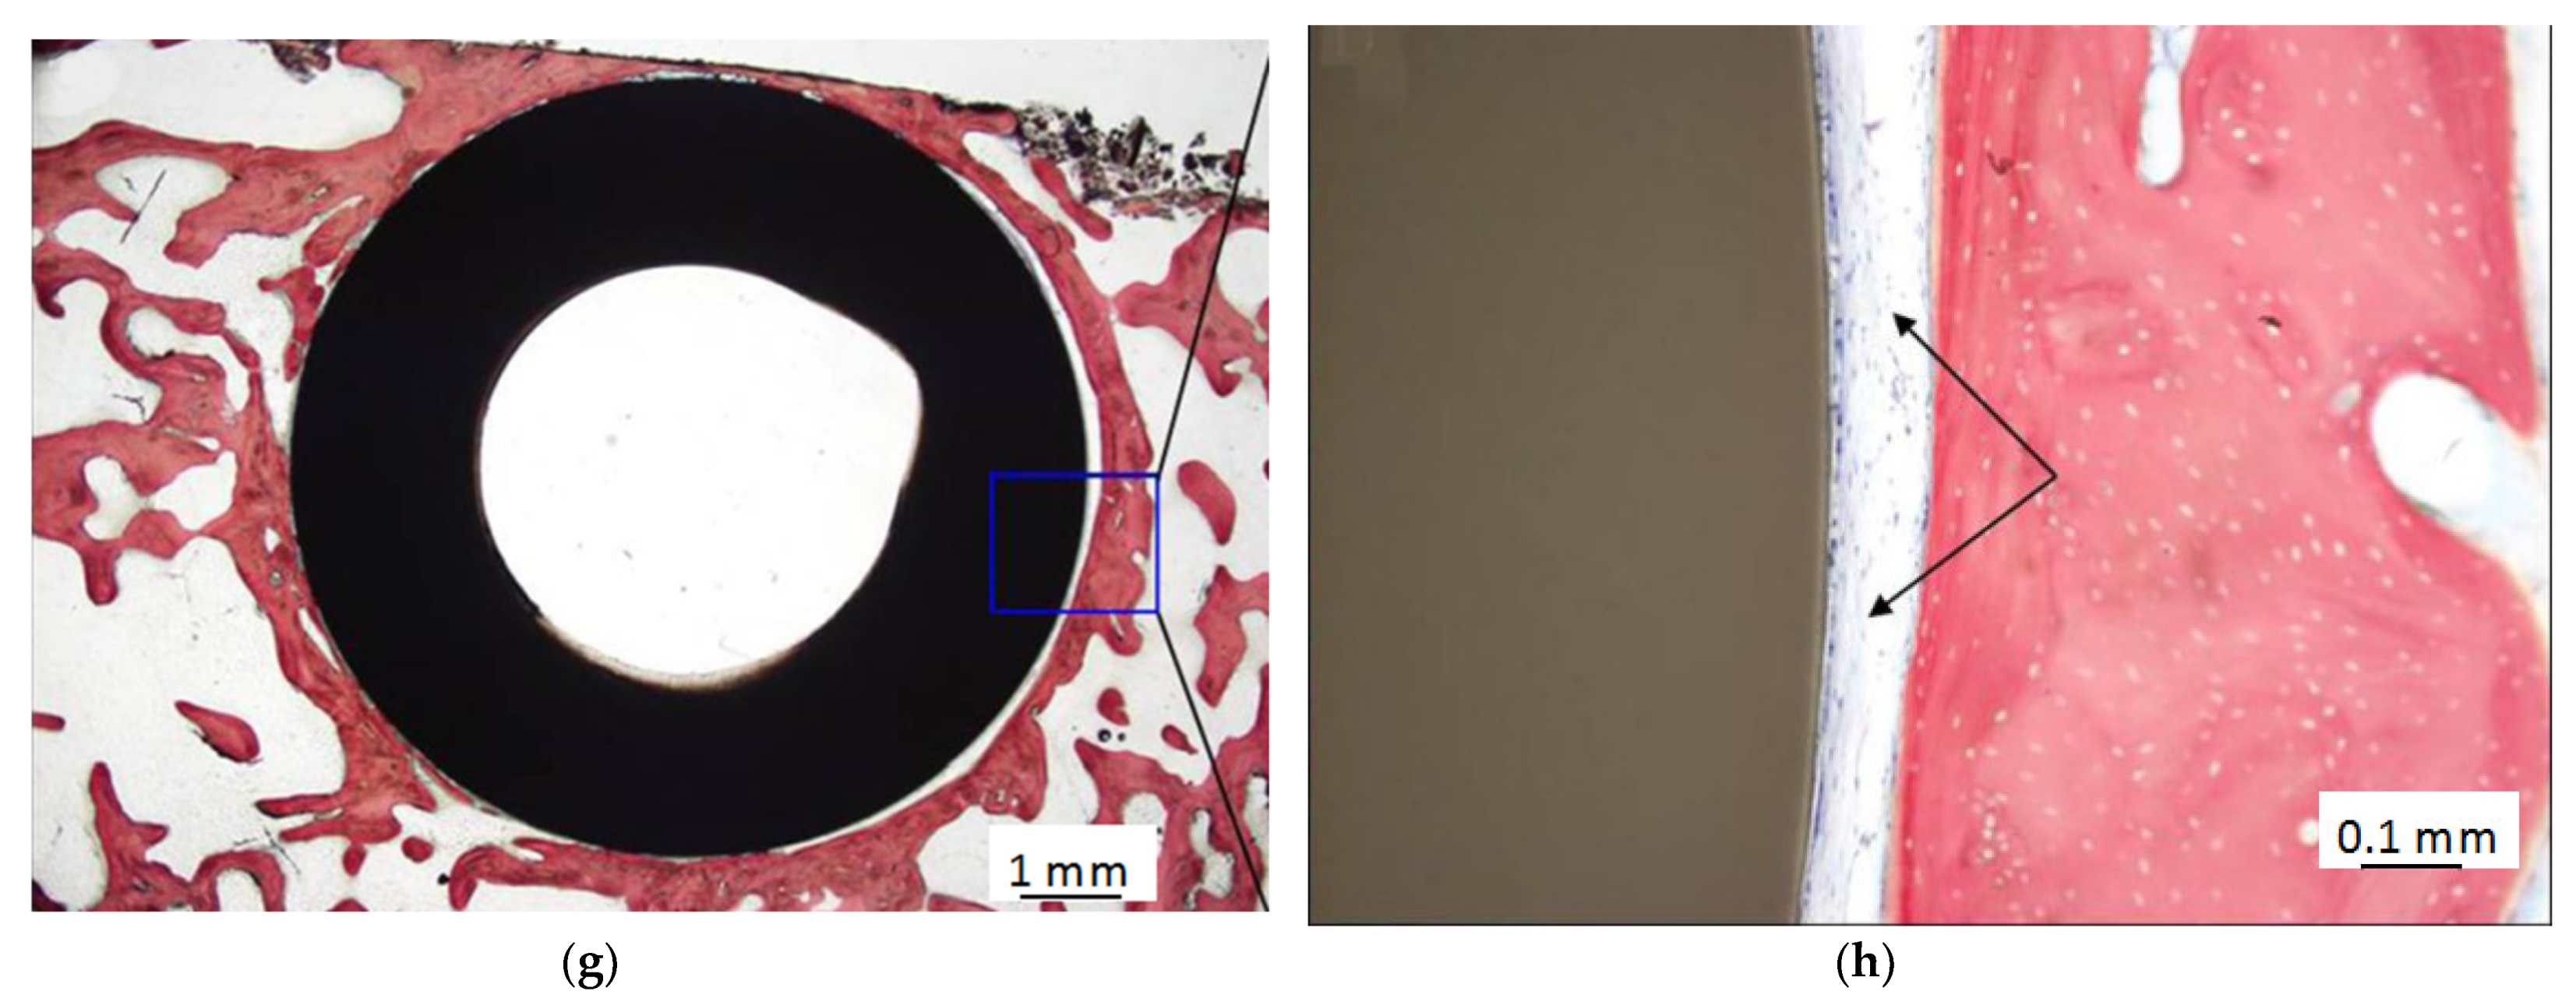

Figure 5.

Histology results for Ti-PEEK implants and uncoated PEEK implants. 12 weeks for Ti-PEEK implants (a,b) and uncoated PEEK implants (c,d); 24 weeks for Ti-PEEK implants (e,f) and uncoated PEEK implants (g,h). Black arrows: fibrous connective tissue. H&E stain. Bar = 1 mm (a,c,e,g); 0.1 mm (b,d,f,h). (Reproduced from [72], with permission from © 2018 Dovepress).